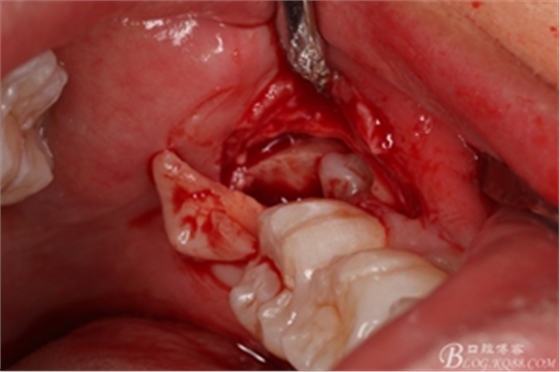

圖10. 翻開(kāi)瓣。38牙冠還有部分骨質(zhì)覆蓋,遂用高速牙鉆去骨

圖11.去骨---暴露出38的牙冠最大周徑

圖12.高速牙鉆分牙

圖13. 分開(kāi)的38牙冠和牙根

圖14. 分別取出38分開(kāi)的牙冠